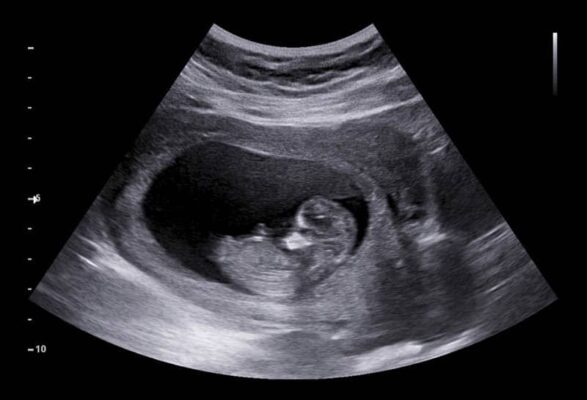

Siêu âm 2D

Siêu âm 2D là loại siêu âm phổ biến nhất và cũng là loại đơn giản nhất. Nó tạo ra hình ảnh phẳng của thai nhi. Và được sử dụng để kiểm tra sức khỏe, kích thước, cân nặng, số lượng, vị trí của thai nhi trong tử cung. Và phát hiện các vấn đề khác liên quan đến sức khỏe.